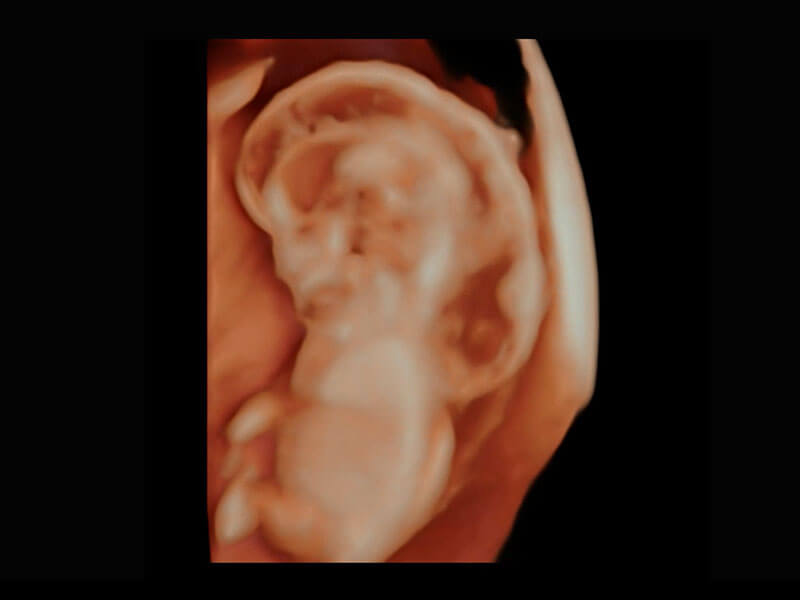

早孕筛查

P60在胎儿早孕期超声筛查中为您带来优异的图像质量。

• 高分辨率容积成像-早孕胎儿

• 胎儿体循环